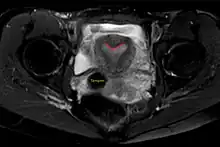

| Arcuate uterus (marked in red) seen on MRI | |

The arcuate uterus is a form of a uterine anomaly or variation where the uterine cavity displays a concave contour towards the fundus. Normally the uterine cavity is straight or convex towards the fundus on anterior-posterior imaging, but in the arcuate uterus the myometrium of the fundus dips into the cavity and may form a small septation. The distinction between an arcuate uterus and a septate uterus is not standardized.

Helpful techniques to investigate the uterine structure are transvaginal ultrasonography and sonohysterography, hysterosalpingography, MRI, and hysteroscopy. More recently 3-D ultrasonography has been advocated as an excellent non-invasive method to delineate the condition.[5]